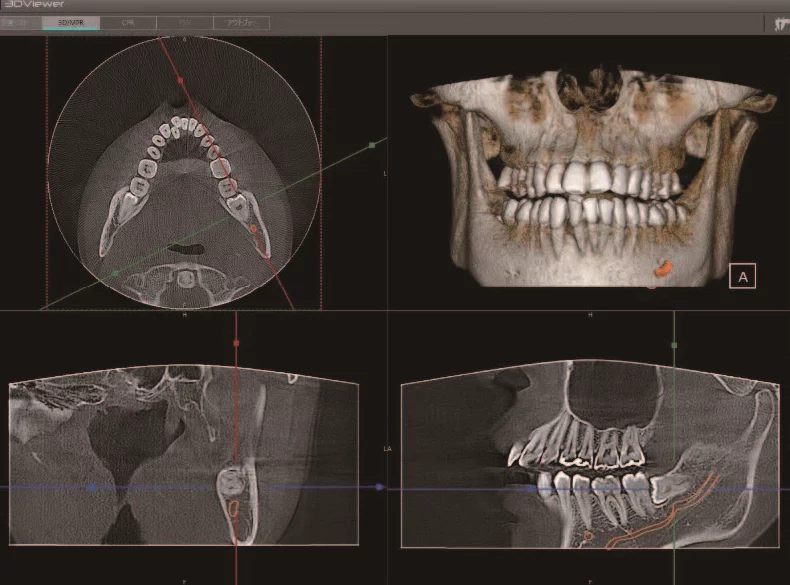

One of the most underestimated values of dental CBCT that we constantly hear from dentists is the increase in case acceptance. When it comes to helping a patient visualize the recommendation of the dental professional, there are few tools more effective than the three-dimensional cross section of the patient’s anatomy that can be rotated and viewed from any angle. Using this tool, the dental professional can clearly explain the recommended plan, which makes the patient dramatically more comfortable and confident.